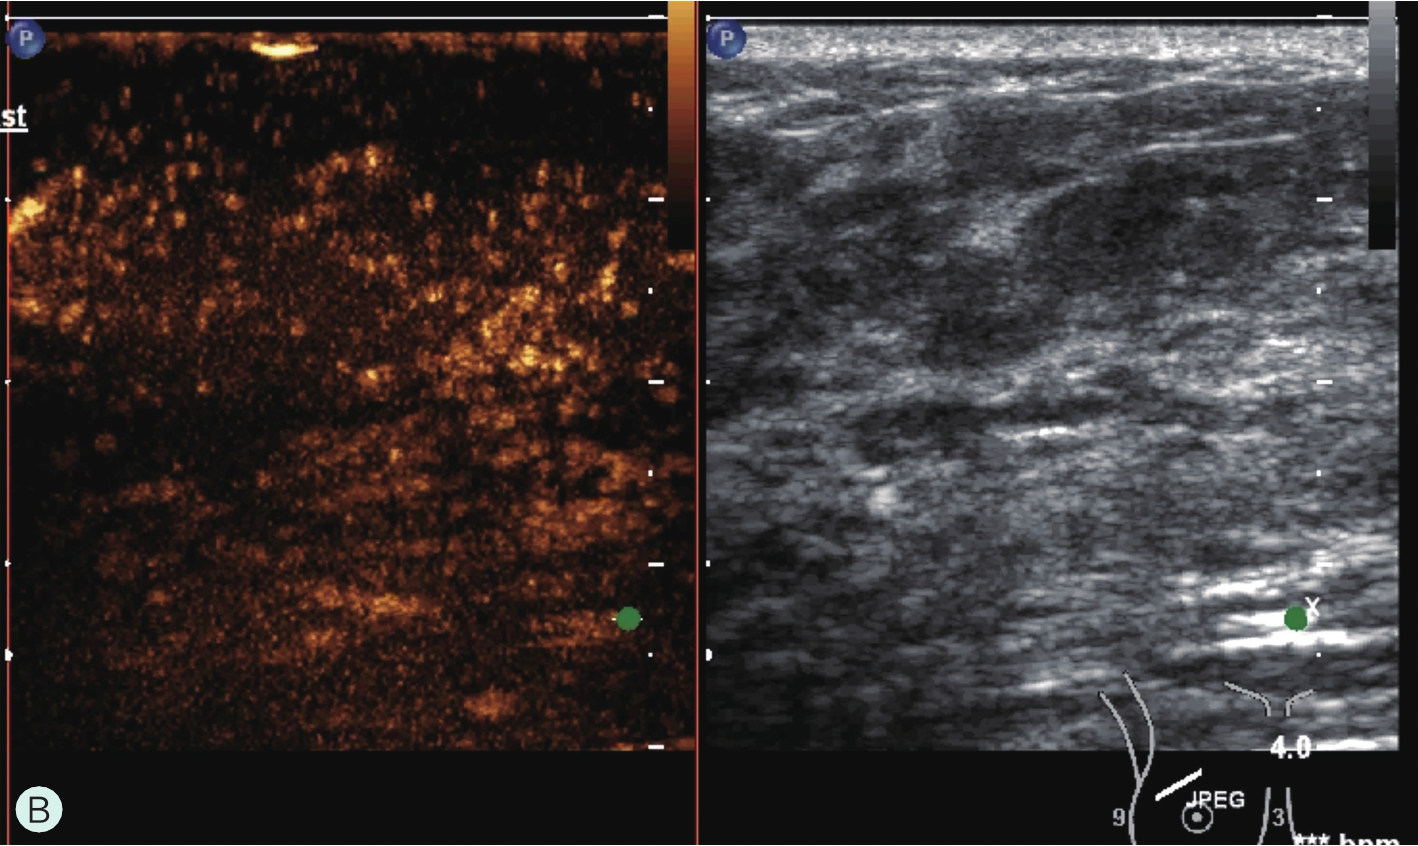

图1-4-3 CEUS时不同乳腺腺体增强强度

A.CEUS背景极少强化;B.CEUS背景轻度强化;C.CEUS背景中度强化;D.CEUS背景重度强化